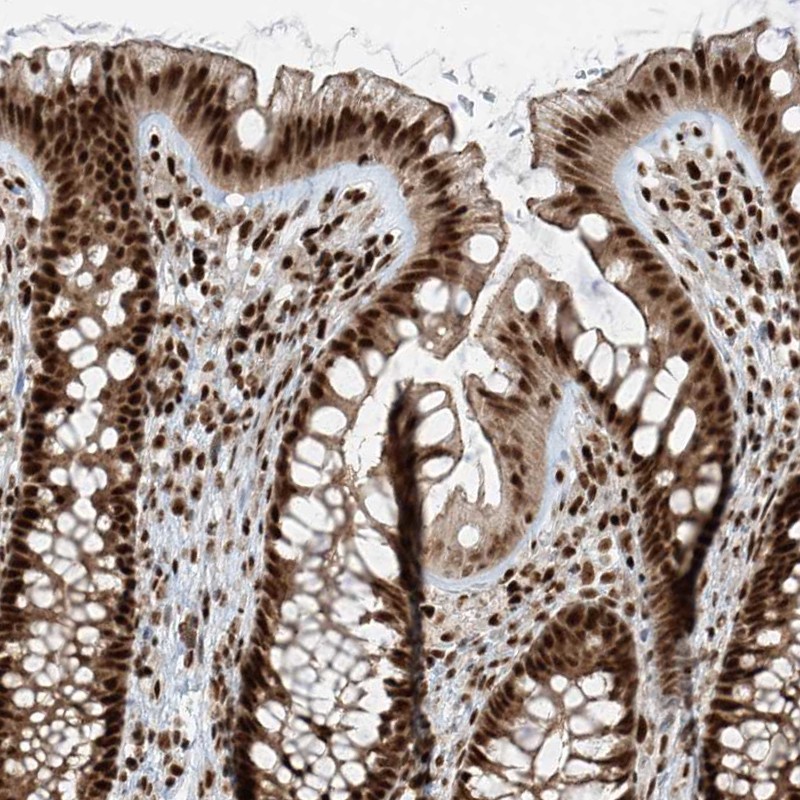

Immunohistochemical staining of human colon shows strong nuclear positivity in glandular cells.